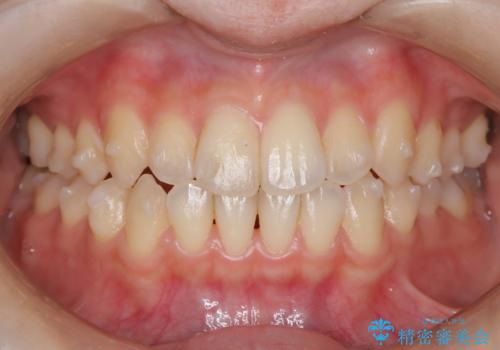

前歯のガタつき、下顎の前突感を治したい インビザライン矯正例

- 治療計画

- 学生時代に矯正治療を経験されていましたが、その後の後戻りによる前歯の叢生・下顎の前突感を主訴に来院されました。叢生や口元の突出感が軽度であった為、非抜歯にて側方拡大やIPRを組み込んでインビザラインにて治療を計画しました。前歯部にクロスバイトがあり、治療途中に上顎前歯が下顎前歯を乗り越えなければならない時期もありましたが、患者様の協力的なマウスピース装着もあり、良好な配列を達成しました。上下左右の親知らずは、当院にて矯正開始前に抜歯しました。